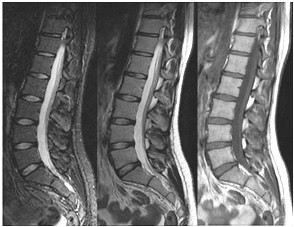

Które kolejne sekwencje badania kręgosłupa lędźwiowego uwidoczniono na przedstawionych obrazach?

A. Sag T2, Sag STIR, Sag T1

B. Sag STIR, Sag T2, Sag T1

C. Sag T2, Sag T1, Sag STIR

D. Sag T1, Sag STIR, Sag T2